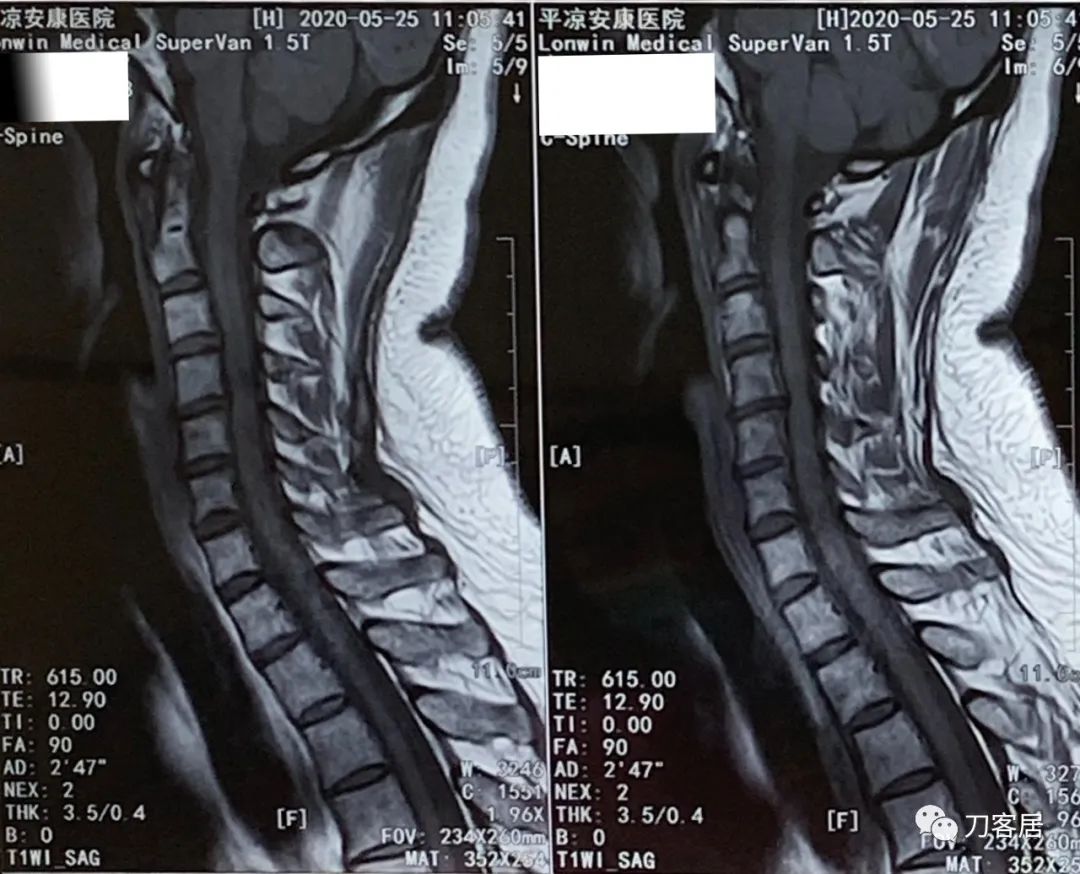

患者回家后又到当地医院做颈椎MRI检查。

图13. 20200525平凉安康医院颈椎MRI01

图14. 20200525平凉安康医院颈椎MRI02

图15. 20200525平凉安康医院颈椎MRI03

图16. 20200525平凉安康医院颈椎MRI04

2020年5月25日做的颈椎MRI并没有新的发现,仍然是颈3-6椎间盘变性及轻度突出,颈6-7椎间盘变性并膨出,颈椎生理曲度不稳,局部反弓。